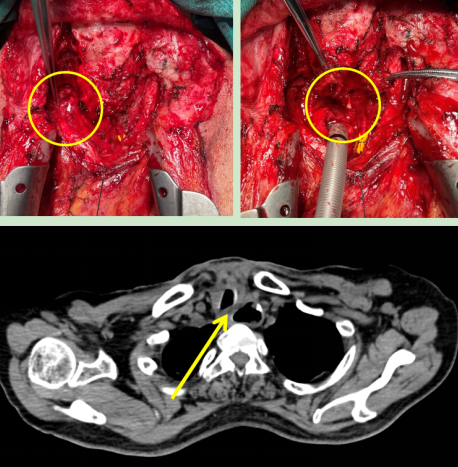

圖2:術中情況(左)喉返神經(jīng)監(jiān)測儀監(jiān)測喉返神經(jīng),(右)離斷氣管暴露食管瘺口;

(下)術后CT顯示原氣管食管間瘺口已修補。

在與患者及家屬充分溝通后,胡楊團隊為患者行“經(jīng)頸部及正中開胸氣管食管瘺修補術,胸大肌帶蒂肌瓣轉(zhuǎn)移成形術”。術中使用喉返神經(jīng)監(jiān)測保護喉返神經(jīng),使用帶蒂胸大肌肌瓣隔絕氣管與食管間瘺口。手術順利完成,術后患者未發(fā)生聲音嘶啞。

術后第五天,患者突然出現(xiàn)頸部皮下氣腫,經(jīng)檢查是因為之前院外手術形成的瘢痕,導致氣管缺血壞死,出現(xiàn)氣管吻合口瘺。這是多次手術的患者術后可能出現(xiàn)的問題之一,處理極其困難,若處理不當極易造成慢性胸骨感染,甚至威脅生命。胡楊副主任醫(yī)師立馬安排第二次手術,術中使用另一側(cè)帶蒂胸大肌肌瓣修補并加固了氣管瘺口,術后復查顯示氣管瘺口成功修補。